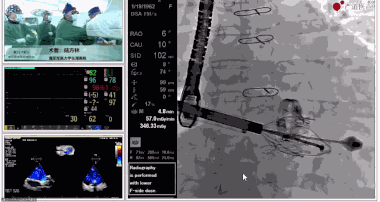

圖片

▲瓣膜植入過程

在手術(shù)直播中瓣膜植入過程不到10分鐘,手術(shù)獲得圓滿成功,充分體現(xiàn)徐志云、陸方林團(tuán)隊(duì)技術(shù)精湛,團(tuán)隊(duì)協(xié)作默契及器械的優(yōu)越性。